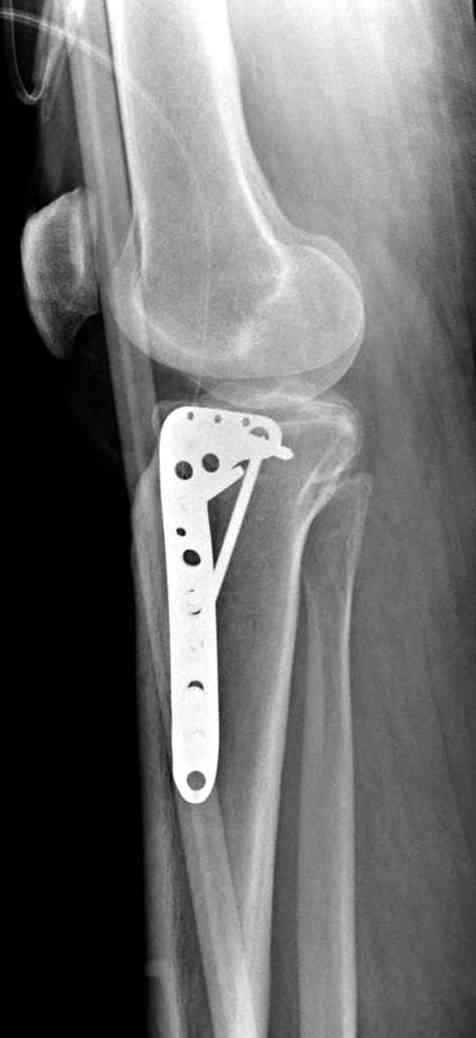

центральная импрессия, а при ипрессии с краевым переломом - после приподнимания импрессии опорная (Butress) пластина, как на снимке.

Из медиального окна можно приподнять латеральную

импрессию. Фиксация тремя параллельными шурупами в

эпифизарной части над импрессией. Создается крыша,

которая предупредит коллапс. На образовавшуюся полость - костная пластика из аутокости или синтетический заменитель. Мы применяем Osteoset в 4-5 мм диаметре таблеточки или иньекционную форму Prodens.